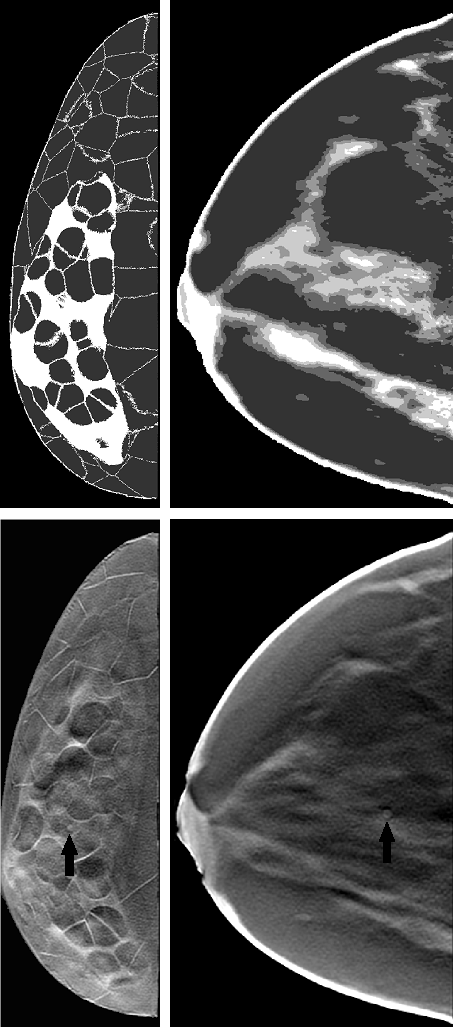

Figure 1 shows sample slices of both types of phantoms on the top. The transitions in XCAT breast phantoms from 100% glandular to adipose tissue have intermediately dense (25%,50%, and 75%) voxels while these transitions are sharp (100% dense to adipose) in Bakic phantoms. The XCAT breast phantoms lack small structures such as cooper‘s ligaments. Erickson et al. erickson2016population noted that the ”lack of very fine-detail structures like cooper‘s ligaments can negatively impact the realism of digital phantoms”. References sturgeon2016eigenbreasts ; chen2017high ; rajagopal2018evaluation tried different methods to improve XCAT breast phantoms, but these phantoms were not released publicly.

The lesion targets were homogeneous spherical masses with a 3-mm diameter. While this is smaller than the average lesion sizes detected by the current DBT systems, VITs are also aimed at evaluating future imaging system designs. This signal size of 3-mm was also chosen to achieve sufficient task-challenge without requiring to artificially alter attenuation values of the signal and to the capture the human observer performance trends more accurately for a range of breast densities. An abnormal case was generated by substituting the lesion into the randomly selected location in the glandular region prior to the projection imaging. The lesion contrast or local glandularity were not matched between phantom types while selecting lesion locations as absolute performance was not relevant for this study. The simulated mass was assumed to have an energy-dependent attenuation coefficient for invasive ductal carcinoma as reported by Johns and Yaffe.johns1987x Eight abnormal cases and one normal case were formed for each phantom. The projections were acquired using Siddon’s ray tracing method siddon1985fast to model x-ray transmission through the breast. Two different sets of projections were generated with different phantom types. In order to filter the random noise, an adaptive Wiener filter based denoising algorithm was applied on each projection.lim1990two ; vieira2013effect The denoising algorithm was shown to reduce the noise effectively in our prior work kavuri2020relative . Each data set was acquired over an angular span of with projection number {3, 7, 11, 15, 19, 21, 25, 31, 35, 41, 45} by keeping the total dose steady at 1.5 mGy for each DBT acquisition. Feldkamp filtered back-projection (FBP) algorithmfeldkamp1984practical was used for image reconstruction. A three-dimensional Butterworth filter with a cutoff of frequency 0.25 cycles/pixel was applied on reconstructed volumes. In-plane DBT images of 1-mm thickness were produced by applying a boxcar averaging. Eight lesion-present (abnormal) and eight lesion-absent (normal) images were created for each phantom for the human observer studies as described in our earlier workdas2015examining . A set of 96 images were produced from the six phantoms of each phantom type for a given projection number. Figure 1 shows sample 1-mm abnormal DBT slices of both types of phantoms on the bottom.

In our studies, each human observer was tasked with search and localization of a 3-mm lesion within the displayed DBT image slice (similar to the ones shown in fig 1). Figure 3 shows sample regions of DBT slices with lesion at the center of region to illustrate the changes in the visibility of the signal for varying number of projections in both types of phantom backgrounds. The signal is better visible in Bakic phantom background for the acquisition configuration of 35 projections, whereas the signal is better visible in XCAT breast background for the acquisitions of 11 to 35 projections. Figure 4 presents LROC plots for the three observers, for a sample acquisition of 35 projections over arc span, in both phantom backgrounds. The y-axis of the LROC represents the joint probability of correctly localizing a lesion in a case reported as positive. Therefore, the curve reaches up to the percentage of cases with correct lesion localization. The LROC AUC values above zero are considered as better than guessing as the likelihood of guessing the lesion’s location is zero. Figure 5 shows the average performance of the three observers in both Bakic and XCAT breast phantom images. Error bar lengths indicate twice the standard error of the three observers’ AUC values. We observed a greater improvement in performance up to 11 projections in XCAT breast phantom backgrounds and a steady performance thereafter. This corresponds to an arc sampling of approximately between adjacent projections for peak performance. In Bakic phantom backgrounds, observers’ performance improved up to 25 projections and required finer arc sampling of approximately to achieve peak performance. We also plotted the detection performance separately for 25% dense and 50% dense slices, where 25% dense indicates easy level of task difficulty while 50% dense indicates higher level of task difficulty. Regardless of phantom type, both levels of task difficulty show similar trends and suggest that optimization may not change with the task difficulty, which is in accordance with earlier observations by Zeng et al. zeng2017optimization and Mackenzie et al.mackenzie2021effect . We also noticed in figures 4 and 5 that observers had overall slightly lower performance in XCAT breast backgrounds than in Bakic backgrounds in particular for 25% dense images. This difference can not be attributed to phantom structures necessarily as the local densities in the region where lesions are inserted could also influence these LROC AUC. The magnitude of AUC values are less relevant in this particular study as only relative change in AUC values with changing system parameters (such a number of projection in this study) were used to deduce the final conclusions. The inter-observer agreement, quantified using the ICC, ranged from 0.92 to 0.95 with the average AUC values, suggesting a strong agreement between the observers.